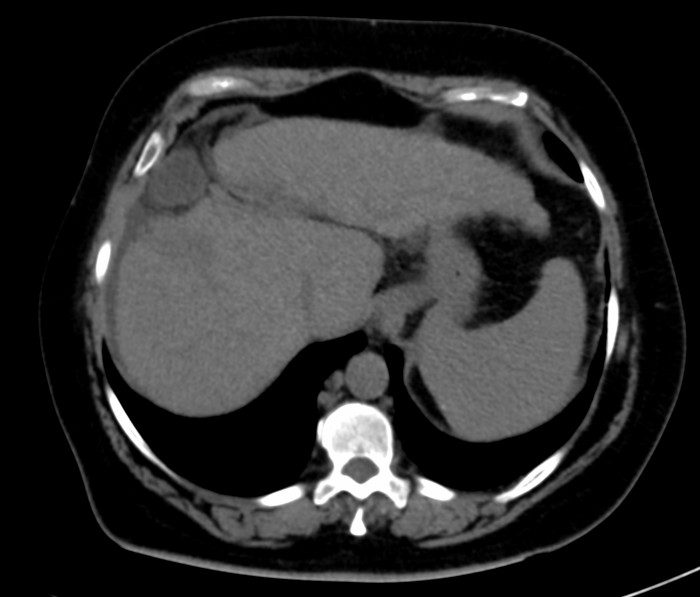

Presentamos el caso de un paciente con diagnóstico de cáncer de mama derecha triple negativo, para el cual se solicita estudio de extensión para estadificación. Se realizó tomografía (TC) de tórax y abdomen simple identificando la vesícula biliar de situación suprahepática (Figs. 1 y 2) asociado a hipoplasia del lóbulo derecho (Fig. 3), así como escaso líquido perivesicular (Fig. 4); no hay lesiones hepáticas que sugieran actividad metastásica. En el resto del estudio no se identificaron alteraciones, ni variantes anatómicas.

Figura 2

TC de abdomen simple en corte axial. Se observa la vesícula biliar ectópica asociada a escaso líquido libre perihepático.